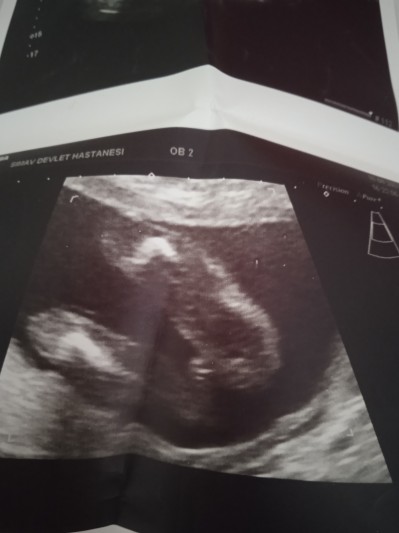

Kızlar 24 haftadayım ama bir türlü bebeğimin cinsiyetini tam bilen çıkmadı biri diyor kız biri erkek hayırlısı olsun Rabbim sağlıkla hepimizin bebeğini kucağına aldırmayı nasip etsin ama insan merak ediyor bu ikinci gebeliğim ilk kızımda böyle şey başıma gelmedi birde siz bakarmisiniz

Gebelik haftası 24+1

Ayy ben erkeğe benzettim ama bilemiyorum yani. Çünkü İnternetten hamile olduğumdan beri ultrason resmi yorumlama araştırdım bana kalırsa erkeğe benziyo.

Kız gibi kordon çıkıntısına benziyor. Erkekte çok daha belirgin oluyor çıkıntı pipi şeklinde